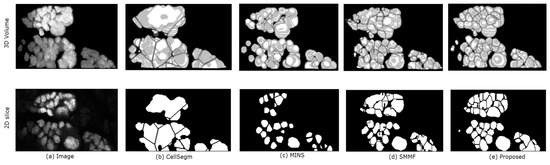

5.1. Evaluation on Sample Dataset

| Algorithm | RI | JI | Oversegmented | Undersegmented | Missing |

|---|---|---|---|---|---|

| CellSegm | 92.24% | 0.659 | 0.005 | 0.00 | 0.00 |

| MINS | 95.86% | 0.713 | 0.003 | 0.00 | 0.025 |

| SMMF | 96.57% | 0.804 | 0.00 | ||

| Proposed | 97.05% | 0.812 | 0.00 | 0.015 | 0.00 |